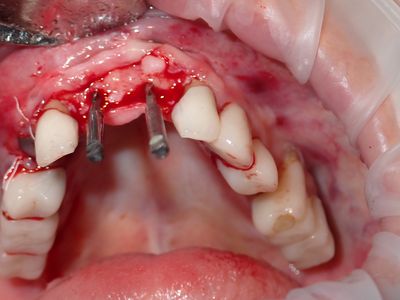

NSankhyan - immediate 13, impls 1121 and 25 with grafting

13 exo, loss of labial plate, implant placed buccal region grafted with sticky bone and collagen membrane soaked in prf fluid. 11/21 limited Labial-palatal width of bone, ridge split to 5mm, osteotomies prepared to about 2mm, remainder with densah drills, implants placed with ample bone, buccal grafted with same sticky bone. densah drills used for apical portion of 25 implant, soft bone, implant placed